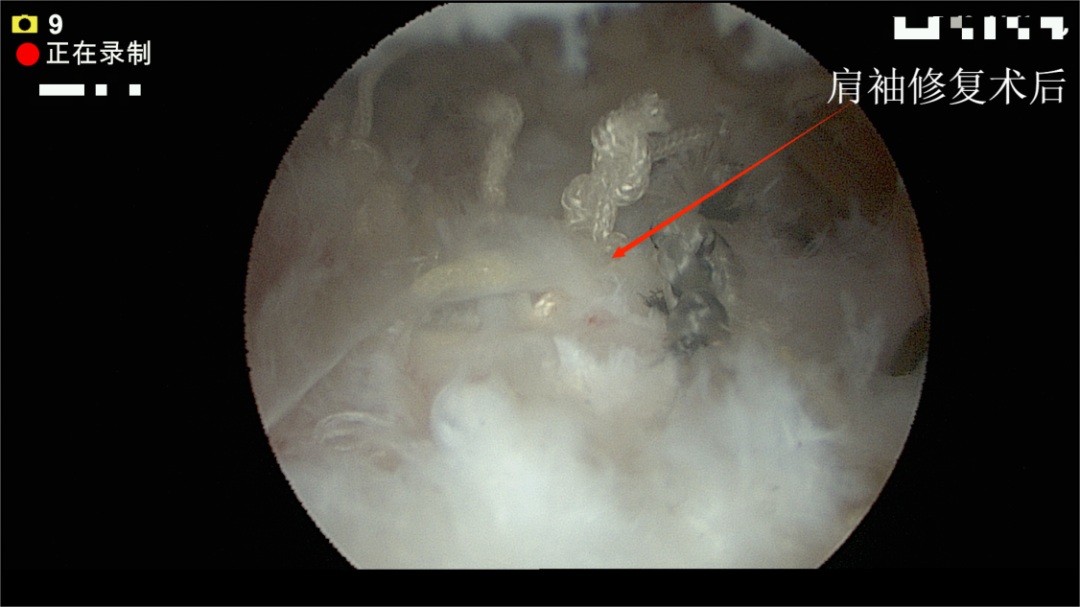

关节镜下:肩袖修复术后

对于这种结构性损伤,保守治疗往往效果有限。骨伤科四病区专家团队为她进行了微创关节镜手术,精准缝合了撕裂的肌腱。术后结合系统康复,她恢复了肩部的力量和活动度。